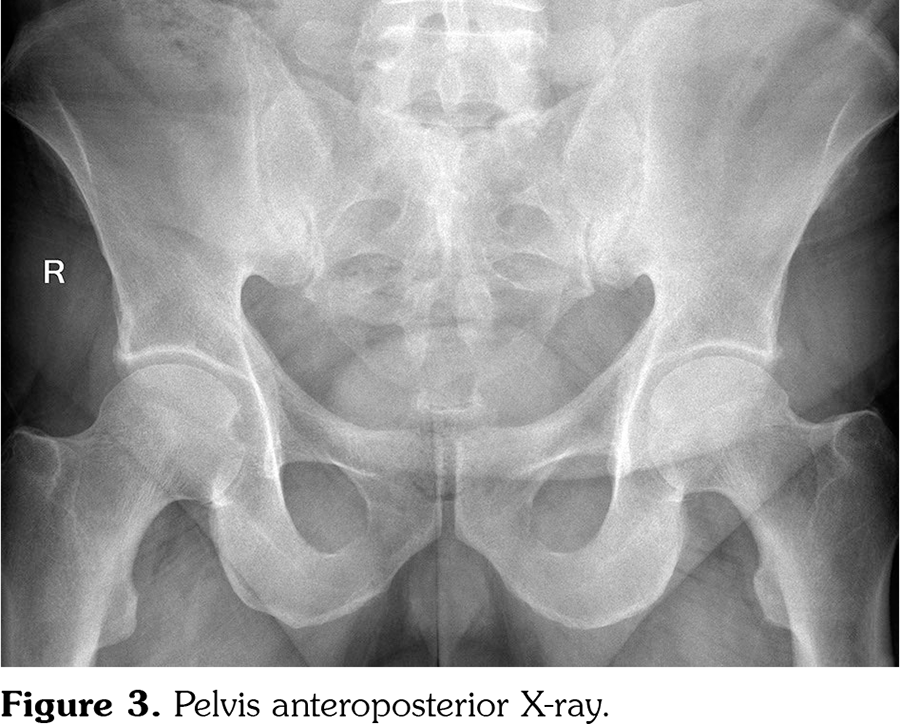

A 45-year-old male patient with RA was referred for newly onset skin rashes on his arms and legs after starting the treatment with tofacitinib (Figure 1). He was taking methotrexate 5 mg/weekly, folic acid 5 mg/weekly and tofacitinib 5 mg twice a day for RA. Disease had started nine years ago, first with pain and swallowing on his ankle. Within one year, arthritis developed on wrist, metacarpophalangeal (MCP) and proximal interphalangeal (PIP) joints, with no involvement in distal interphalangeal (DIP) joints. The patient had no inflammatory back pain symptoms. Psoriasis was not present in his or his family’s medical history. Laboratory tests were negative for antinuclear antibody, extractable nuclear antigen profile, anti-cyclic citrullinated peptide, rheumatoid factor and human leukocyte antigen B27. Erythrocyte sedimentation rate was 26 mm/hour and C-reactive protein was 12.6 mg/L (0-5 mg/L). There were bilateral ulnar styloid erosions, carpal erosions and osteopenia on his hand X-ray; marginal erosions on fifth MCP, second MCP, third PIP joint, subluxation on second MCP joint on right hand; joint erosion and subluxation of first MCP, erosion and joint space narrowing of second PIP joint on left hand (Figure 2). DIP joints were normal on both hands except two osteophytes. On his pelvis anteroposterior X-ray, sacroiliac joint spaces were normal (Figure 3). Patient’s type of joint involvement and radiological findings were consistent with RA but not psoriatic arthritis. In this course, he had used methotrexate, sulfasalazine, leflunomide, hydroxychloroquine and glucocorticoids at different times. Because of the ineffectiveness of the conventional synthetic disease-modifying anti-rheumatic drugs, etanercept was started. Then, etanercept induced skin rashes with unknown characteristics and was stopped subsequently. After improving of the skin rashes, rituximab was started but discontinued due to the ineffectiveness. Tofacitinib was started when his disease activity was high (disease activity score-28 [DAS28] >5.1). Skin rashes appeared on the third month of the tofacitinib therapy while disease activity was low (DAS28=2.8). We consulted the dermatology. Dermatological examination revealed multiple, clearly demarcated, silvery, squamous and erythematous papules and plaques on the arms, legs, and ankles. Skin biopsy was performed. Epidermal parakeratosis, hyperkeratosis, focal hypogranulosis, and acanthosis with elongation of the rete ridges were observed in the skin biopsy. He was diagnosed with psoriasis. We decided that tofacitinib induced psoriasiform lesions, so tofacitinib was discontinued and leflunomide was started. After two months, lesions were improved. A written informed consent was obtained from the patient.